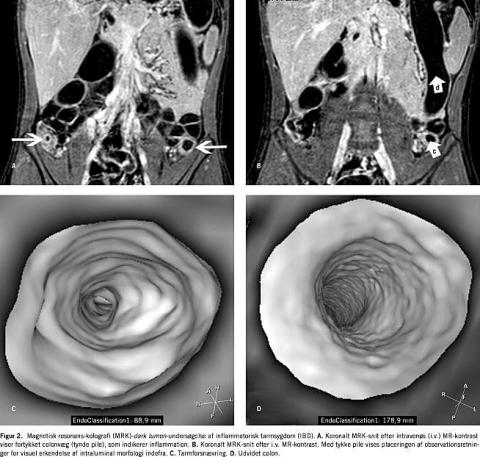

Udviklingen af kraftigere computere og MR-skannere har gjort det klinisk muligt at undersøge hele colon ved hjælp af MRK. Primære undersøgelser tyder på, at MRK er egnet til påvisning af kolorektale tumorer (polypper eller cancer) (Figur 1 ) og diagnostik af inflammatorisk tarmsygdom (IBD) (Figur 2 ).

Patienter med colitis uclerosa [10, 11] og Crohns sygdom [11, 12] gennemgår hyppige diagnostiske undersøgelser i sygdomsforløbet. Tyndtarmsundersøgelse, røntgenundersøgelse af colon, koloskopi og til dels CT-skanning anvendes i det diagnostiske arsenal. Ulempen ved den konventionelle koloskopi er, at det i ca. 20% af undersøgelserne ikke lykkes visuelt at erkende den proksimale colon [7, 8], mens man ved røntgen- og CT-undersøgelser udsætter patienter for ioniseret stråling.

Forbedringen af MR-skannere og tilgængeligheden af kontraststoffer har i den senere tid ført til stigende anvendelse af MR ved IBD [13, 14]. Ved MR ses den ødematøse, velvaskulariserede aperistaltiske og/eller fortykkede tarmvæg samt læsioner uden for tarmen som fistler og abscesser.

MR anvendtes i stigende omfang til diagnostik af tyndtarmsforandringer ved Crohns sygdom [1, 13, 14]. I de senere år er MRK, som benytter planar rekonstruktionsdataanalyse, også blevet anvendt ved IBD i colon [10, 12-14, 36]. Ved IBD koncentreres interessen om de tre kriterier: tykkelsen af colonvæg [10, 14, 37], tarmforsnævring og øget optagelse af kontrast givet intravenøst [10, 14, 38, 39]. Intensitetsstigningen i inflammeret tarmvæg er mindst dobbelt så stor som i en rask tarmvæg, hvilket giver metoden en høj sensitivitet. Tarmforsnævring og colonvægtykkelsen korrelerer med de inflammatoriske ændringer. Desuden er det muligt at identificere inflammerede tarmområder i jejunum og den proksimale ileum, som det kan være problematisk at finde med den konventionelle koloskopi [14]. Intensitetsstigningen er dog afhængig af sygdomsaktiviteten på undersøgelsestidspunktet. Det er derfor ikke mærkeligt, at Schreyer et al [13] fandt, at der er lige så mange publikationer, som viser en god korrelation mellem MR og Crohns sygdom-aktivitetsindeks (CDAI), som publikationer, der viser ringe korrelation. Området er således langtfra færdigudforsket.

Der forligger ikke opgørelse r, der er fokuseret på anvendelsen af virtuel koloskopi ved IBD. Ved virtuel koloskopi finder man kun intraluminal morfologi med detaljer > 5 mm [13]. Derfor kan små colonoverfladedeformationer og erosioner ikke erkendes visuelt.